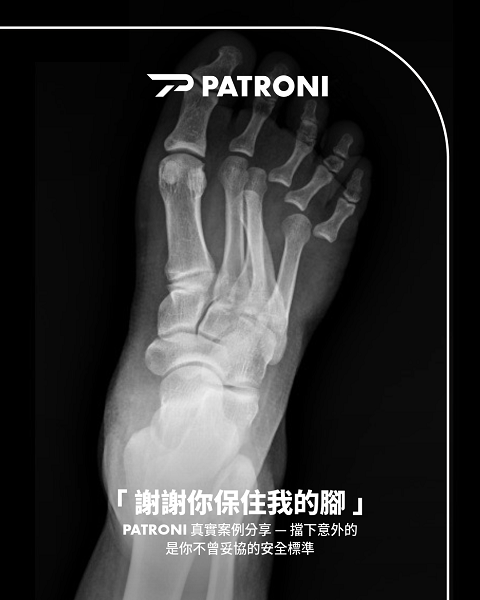

|發生車禍時穿著安全鞋避免了腳趾骨折、削掉等嚴重傷害,但仍舊造成了嚴重脫臼的右腳X光照|照片來源:J先生|

砂石車前保桿直接撞上J先生,強大的力道將他的腳擠向牆面且滑行5-10米。照完 X 光後,醫護人員都感到訝異:他的第四腳趾被擠到第三腳趾下方,嚴重交叉疊狀。我在聽他描述時,忍不住用手指模擬那個位置:「天啊,那樣想說應該是斷了吧?」

腳趾嚴重脫臼,肌肉組織嚴重錯位

雖然骨頭奇蹟沒斷,但傷勢依然複雜。開刀時發現裡面全是血塊,肌肉組織嚴重錯位。

目前J先生的第四、五趾都釘上了鋼釘進行固定與復健。骨科醫師直言,這種撞擊力道腳掌通常早就碎了,能保住骨頭完整性非常少見。